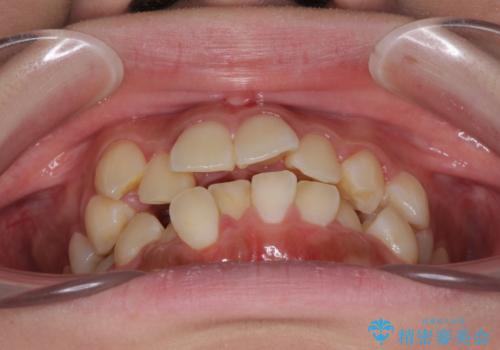

- 八重歯やデコボコをインビザラインで治療したいとのことで来院された患者様です。

インビザライン単体で治療を行うには叢生が強いと判断されたため、事前にワイヤー装置で抜歯矯正を行い、ある程度改善してからインビザラインにて仕上げていくこととしました。